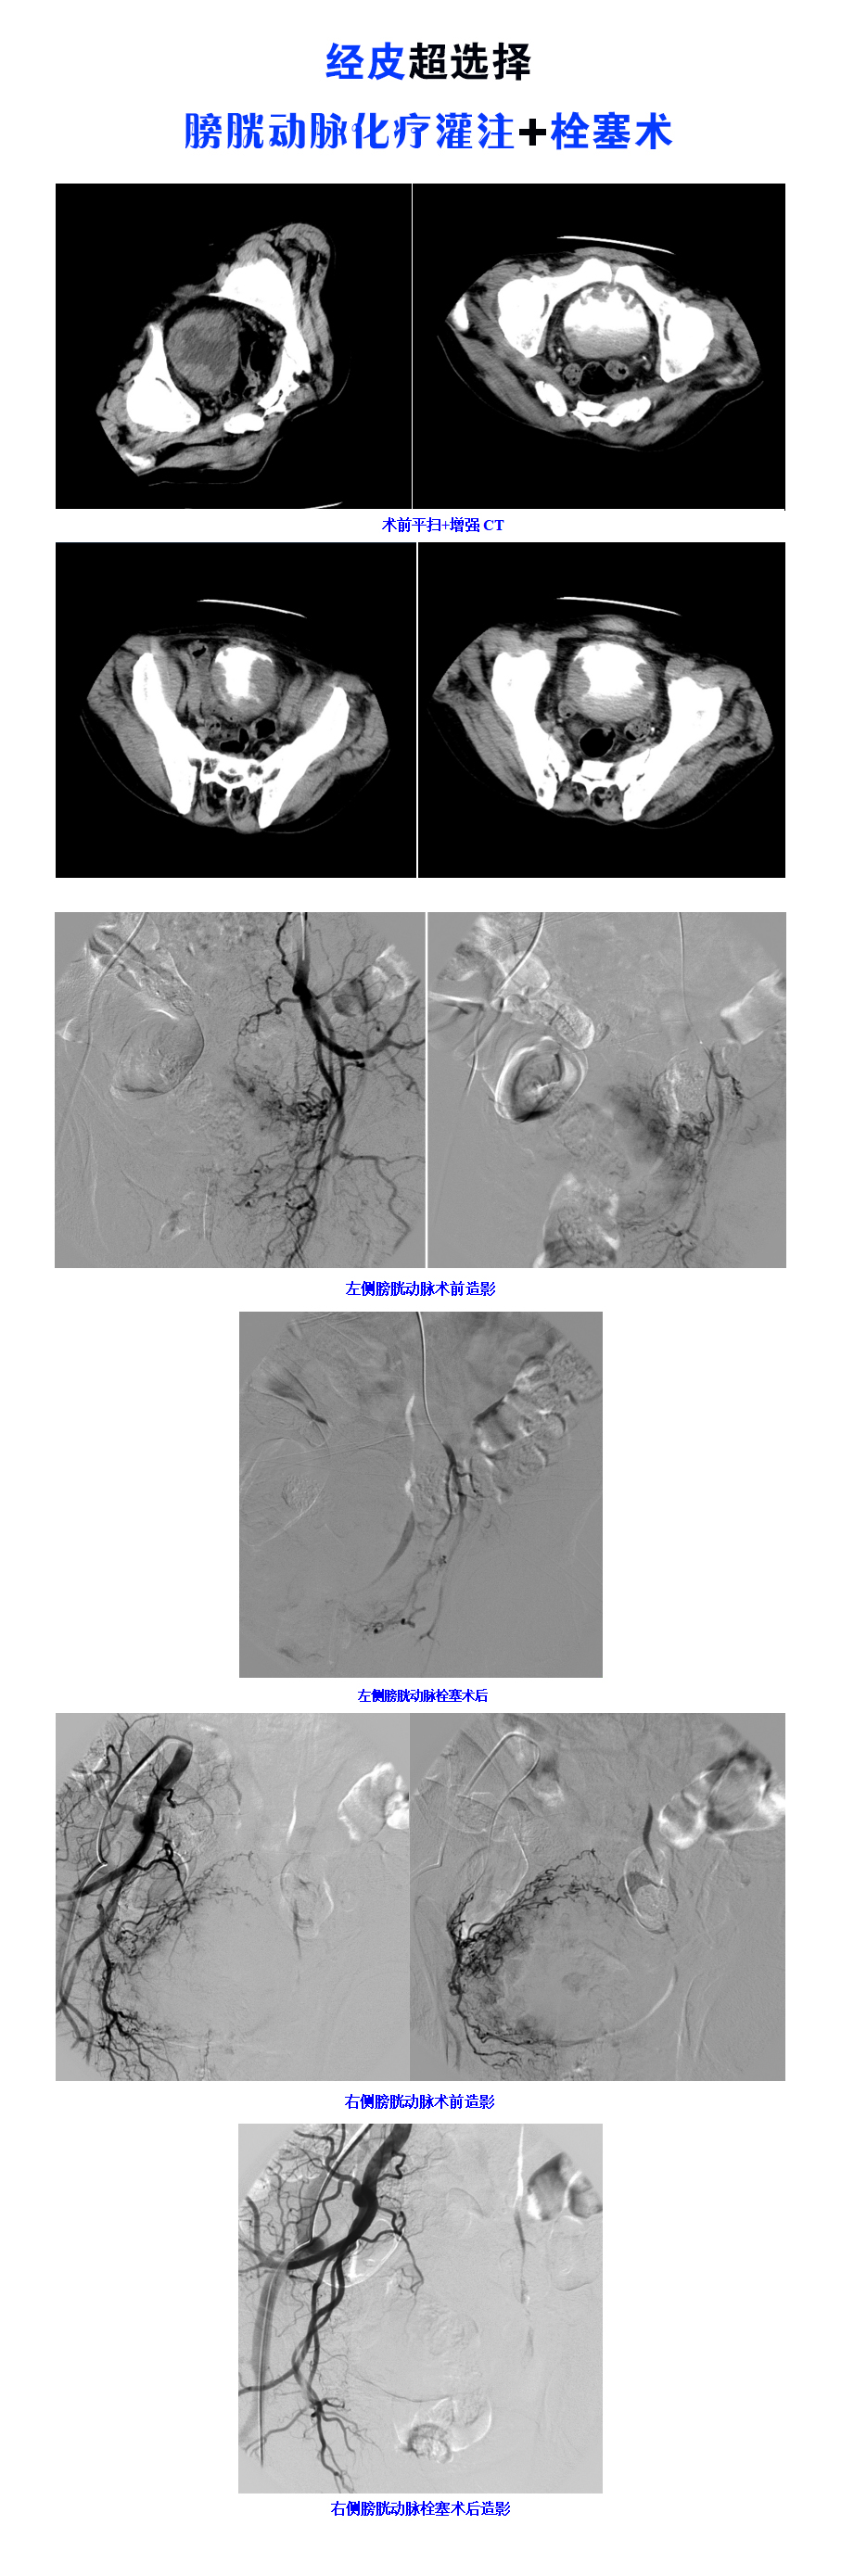

近期,一位因“間斷血尿4個月”的老年男患者慕名到河南宏力醫(yī)院就診。河南宏力醫(yī)院成功為其開展經皮超選擇膀胱動脈化療灌注+栓塞術,患者一周后順利出院。

河南宏力醫(yī)院泌尿外科醫(yī)生接診后,詳細詢問該患者病史,建議住院進一步診治。治療過程中完善下腹部增強CT提示:晚期膀胱癌。泌尿外科立即組織科內討論后,特邀介入科會診,介入科副主任龍軍強查視患者并全面評估后,結合患者各項輔助檢查結果及臨床體征,符合經皮膀胱動脈栓塞術適應癥。在介入科醫(yī)、護、技的通力配合下,為患者行經皮超選擇膀胱動脈化療灌注+栓塞術,術后在泌尿外科精心治療、護理下,患者血尿癥狀明顯好轉,一周后出院。近日隨訪過程中,該患者對治療效果非常滿意。

膀胱癌是泌尿系統(tǒng)最常見的惡性腫瘤,根治切除是首選,但對老年、晚期、出血嚴重患者,超選擇膀胱動脈化療灌注+栓塞術較有優(yōu)勢。